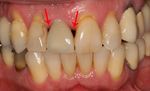

زراعة الأسنان أو غرس الأسنان dental implant، هي تدخل جراحي يتعامل مع عظام الفك أو الجمجمة لدعم تعويضات الأسنان مثل التاج، الجسر، طقم الأسنان، التعويضات الوجهيية أو التي تعمل كأداة تقويم. أساس زراعة الأسنان الحديثة هو عملية حيوية تسمى osseointegration حيث المواد مثل التيتانيوم، تشكل رابطة قوية بالأسنان.

في طب الأسنان، زراعة الأسنان هي كل مايتعلق بزرع المواد الصلبة تحت الغشاء المخاطي السنخي، أو تحت السمحاق، أو في العظم، وذلك للمساعدة على تثبيت الصفائح السنية التعويضية في الفم. والفرق الرئيس بين هذه الزروع والزروع في باقي أنحاء الجسم، كزرع صمام القلب، وعنق المفصل، أن التعامل في الزروع الأخيرة يكون مع مادة غرست في جوف مغلق، أما في الغرسة الفكية فإن بروز المهاميز عبر الغشاء المخاطي إلى جوف الفم يؤدي إلى «غرسة مفتوحة» مما يترك صلة واضحة بين جوف الفم وما فيه من جراثيم والجوف الحاوي للغرسة.